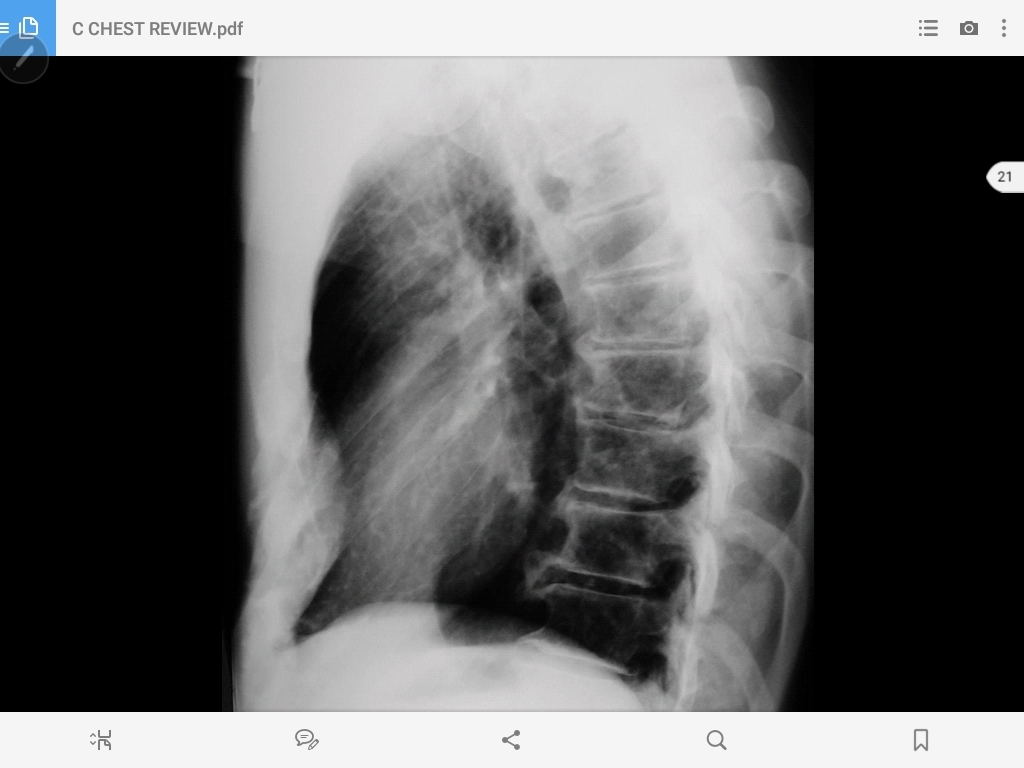

pectus excavatum